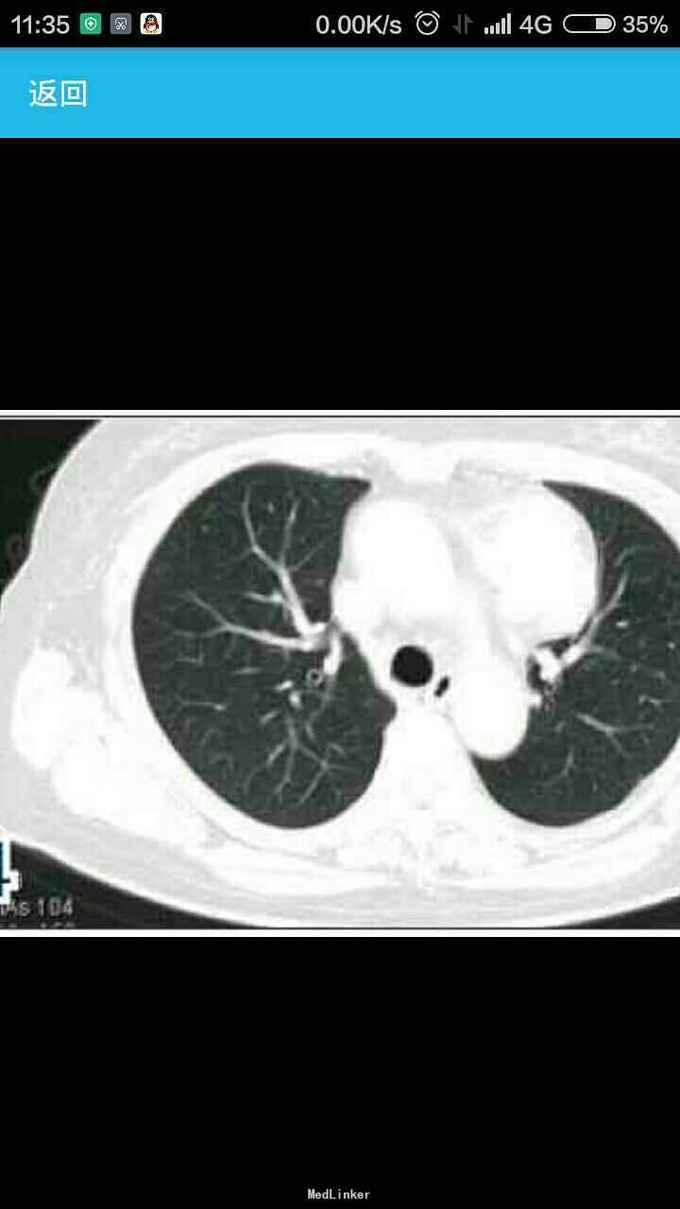

女性,60岁,因左 趾关节红肿、剧痛,红肿弥漫足背 23天来诊,不伴发热,无外伤史, 全身体检无明显异常。 胸片示,左侧前上纵隔占位性病变(图1)。胸部CT示,左侧前上纵隔内见5.7 cm×3.8 cm软组织肿块影,内见斑片状稍高密度影,境界不清(图2——5)。 实验室检查显示,血尿酸517.1 μmol/L(正常值180——357 μmol/L),临床诊断为“急性痛风”,为排除相关疾病作进一步检查。 印象:左侧前上纵隔占位(恶性肿瘤?畸胎瘤?)。 手术结果:肿瘤位于左前纵隔,大小约为8 cm×8 cm ×6 cm,质硬,表面光滑,与心包、无名静脉、肺门粘连(侵犯壁层、脏层、胸膜、肺门、心包、膈肌、膈神经,伴肿大淋巴结)。【病理结果示】(图6):肿块9 cm×6 cm×4 cm,侵犯周围脂肪组织,伴神经内分泌分化。肿块标记:CD5(+)、CD117(+)、嗜铬粒蛋白A(CgA)灶(+)、突触素(Syn,+)、CD56 (-)、细胞增殖因子Ki-67约20%(+)。【诊断】胸腺鳞状细胞癌Ⅱ——Ⅲ级,伴神经内分泌分化。